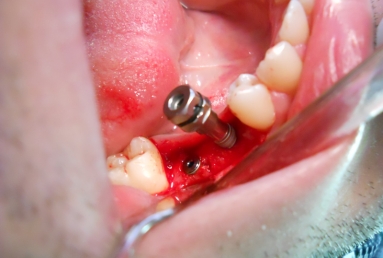

Initial situation: two missing teeth, second lower premolar and first lower molar. two dental implant are integrating in the mandibular bone for 4 months, then, gingival healing caps are applied for 3 weeks. an impression is taken for the dental lab in order to manufacture 2 porcelain fused to metal crowns. they will be screwed directly in the implant body.